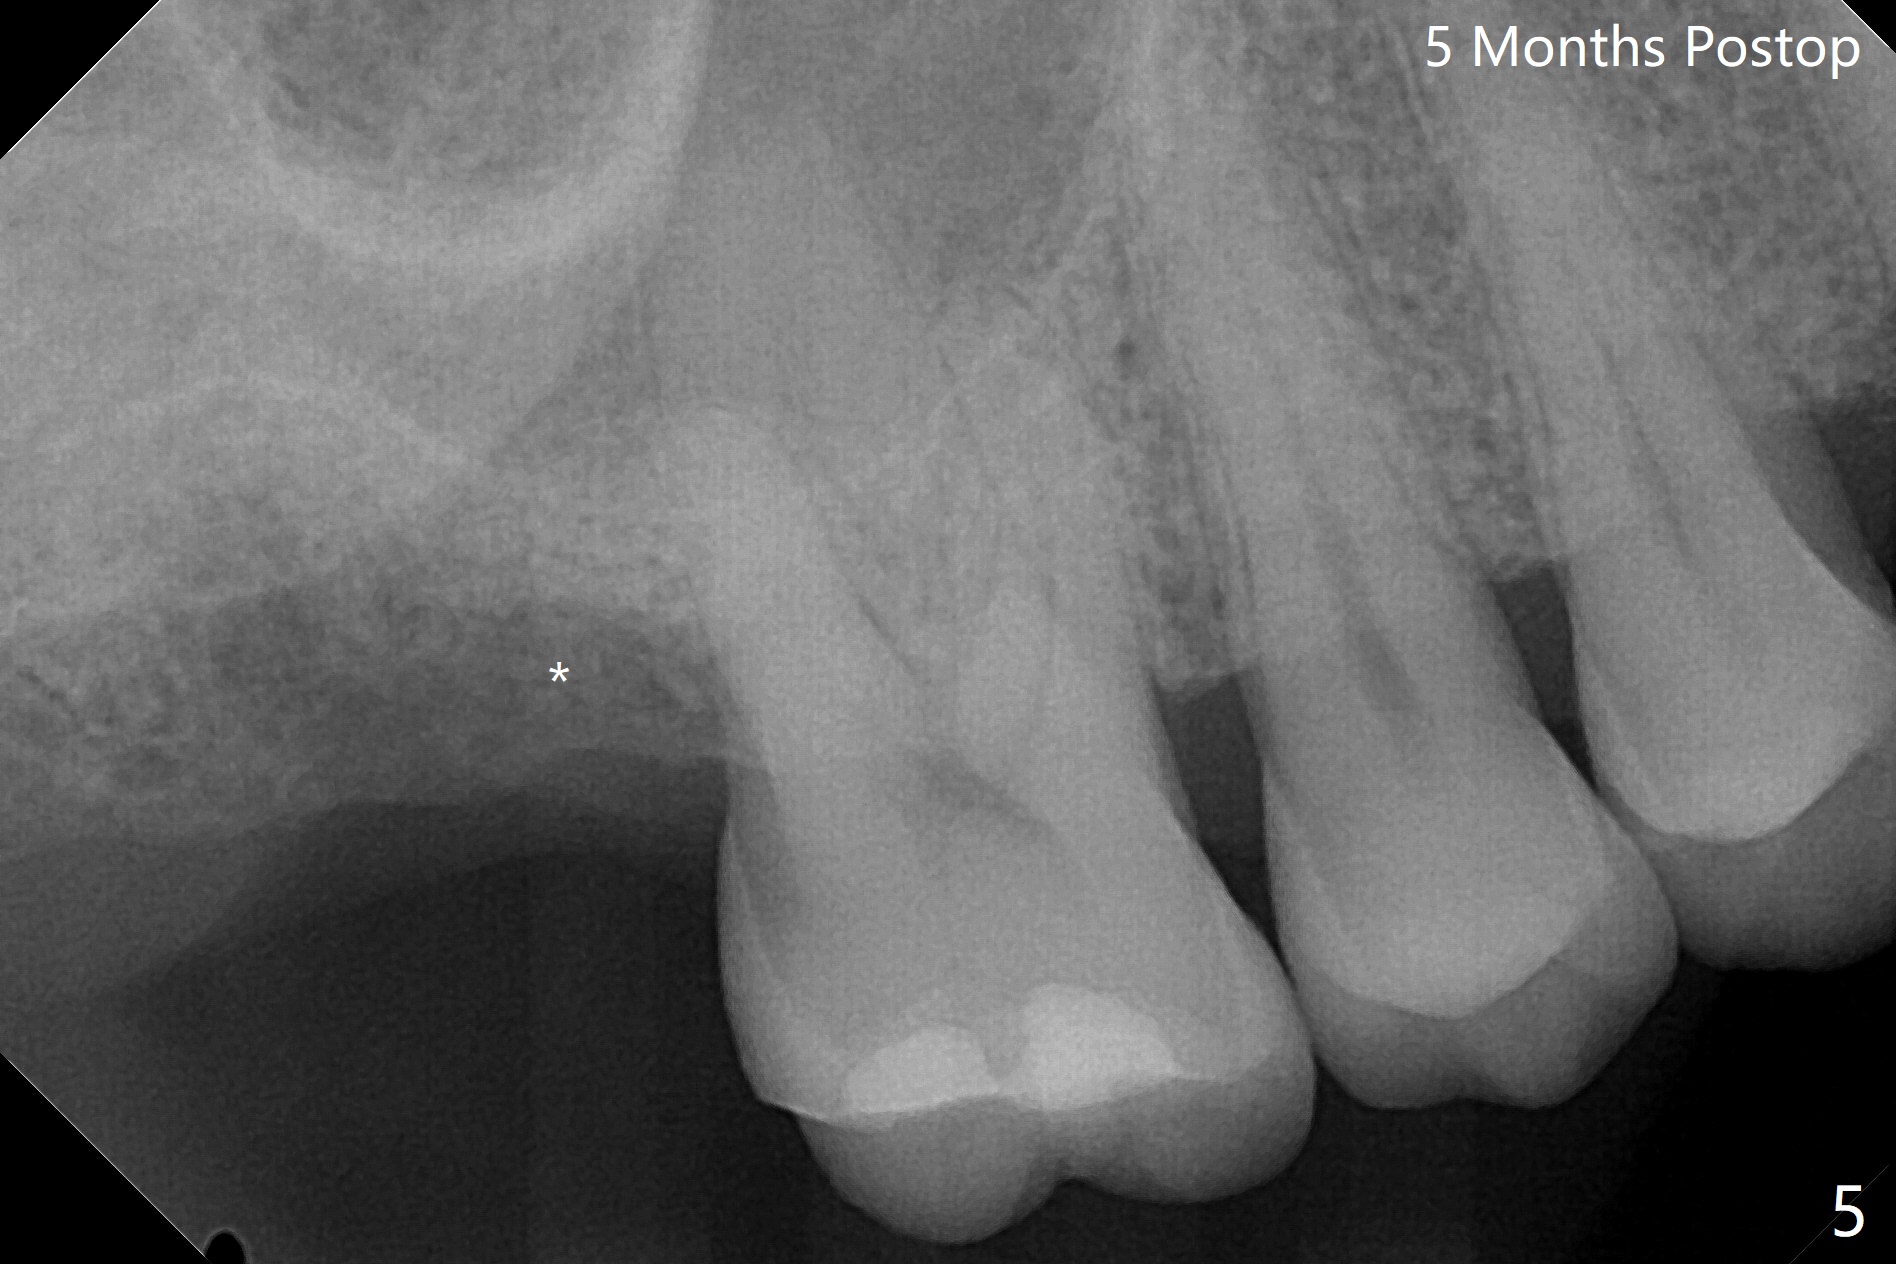

在导航协助下,我们可以一期准确进行上颌窦提升,即刻种植,即刻修复。56岁男(吸烟)右侧上颌窦有粘液囊肿,右上七牙齿折裂(图一(术前):^),CT检查表明植体植入腭侧牙槽窝比较合适(图一:>)。为了减少对囊肿损伤,我们使用导板(图二 *)完成初步钻洞,接近上颌窦底板,然后放置粘性骨(>),用4x10毫米dummy(报废)植体慢速(15 RPM)旋入进行内提升,同时准确控制深度。再次放置骨粉,使用4.5x10毫米报废植体上推;最后放置骨粉后(图三 >),植入正式植体(5x9毫米,扭力大于35Ncm)和修复基台(6.5x4(4)),怀疑后者没有完全就位,后来使用小的基台(图四,并且调整高度),植体和基台周围放置骨粉(*),然后安置临时牙冠。咬颌面没有接触,临时牙冠主要目的是防止骨粉丢失。反复告诉病人不能咬东西。术后两周病人主诉临时牙冠太大,试图减少颊舌侧向,不幸的是却减少近中远中向,造成临时牙冠不稳定。一周后牙冠和基台松动,取出,放置愈合螺帽,牙槽窝基本愈合。病人将术后近四个月复诊,拍摄根尖片和咬翼片,如果骨质愈合良好,尝试在尚未完全愈合的伤口放置小号愈合基台。术后5个月牙冠粘固后拧紧植体松动,取出(图五(*:缺损)),植骨。四个月后骨质高度近5毫米(图六)。再次植入尽量避免窦膜穿孔(粘液囊肿),塞入PRF膜。Return to Upper Molar Immediate Implant, Prevent Molar Periimplantitis (Protocols, Table) No Deviation 不理想病例 开场白Xin Wei, DDS, PhD, MS 1st edition 08/10/2020, last revision 06/12/2021